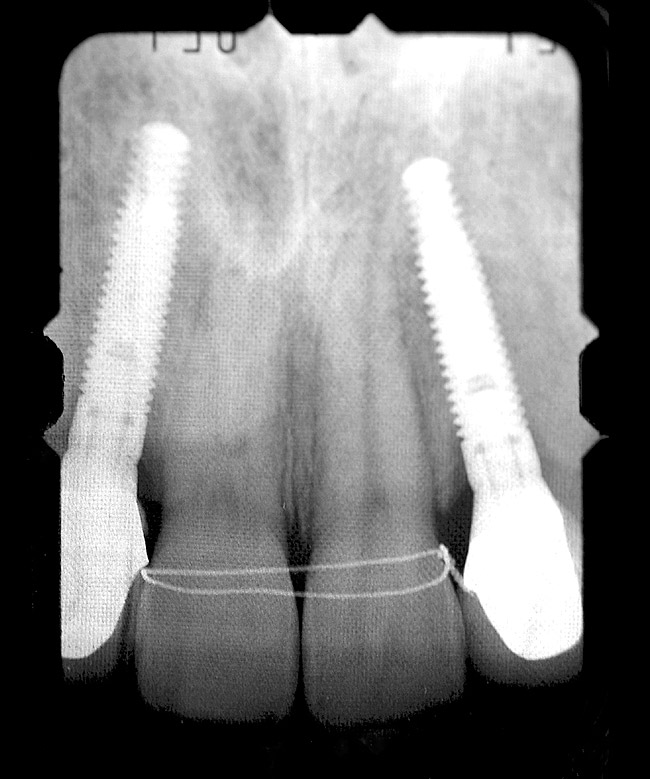

Periapical radiographs were taken to help determine the mesial-distal inclinations of the adjacent tooth roots (Figure 1). The radiographs revealed a serious issue, convergent roots for the right canine and right central, which eliminated that area as a potential implant-receptor site. The space between the left central and canine teeth was minimal, although the roots were relatively parallel. Clinical examination (manual palpation of the root eminences superiorly to the vestibule on the right side) confirmed the root convergence (Figure 2). The flat, wide zone of the keratinized tissue and lack of interdental papilla was evident for the missing right lateral incisor. There was a marked difference in clinical appearance for the left lateral, which could impact the eventual plan of treatment (Figure 3). Other significant clinical findings included bilateral facial bone concavities, which existed as a result of the congenitally missing tooth roots. As a diagnostic cue to the underlying bone topography, it is important to follow the demarcation between attached and unattached gingival tissue, and note the crestal width of the available keratinized tissue (Figure 4).

Figure 1  PRE-TREATMENT DIAGNOSTICS Pretreatment radiographs revealed convergent roots for the right canine and right central.

Figure 1